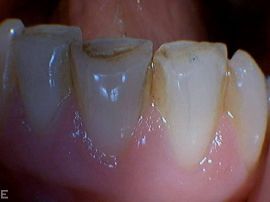

- Metallfreie Keramikkronen und Verblendschalen aus Porzellan (laborgefertigt), vor allem für ästhetisch wichtige Zähne

- Ästhetische Verbesserung von verfärbten oder leicht schiefen Zähnen mit kostengünstigen Komposit-Überzügen